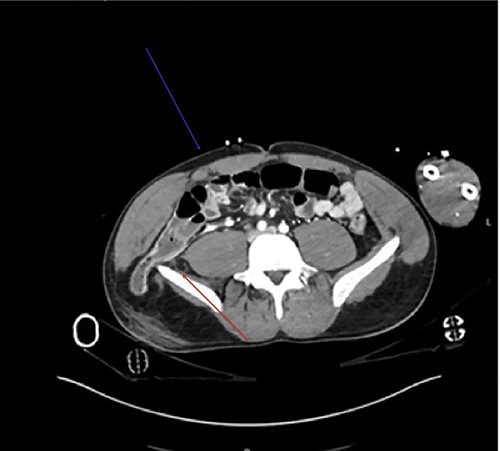

Coronal view showcases the inferior lumbar hernia above the iliac crest (red arrow).